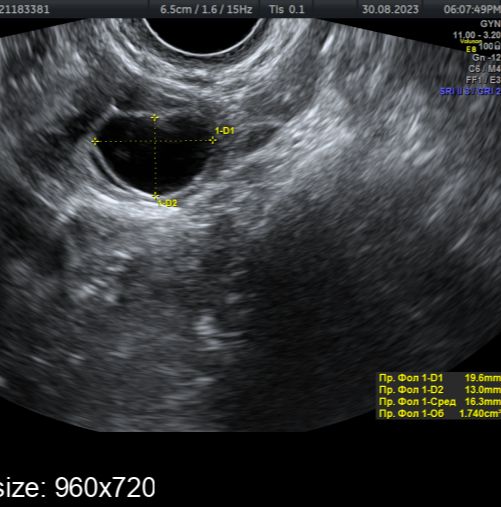

. 30 августа vs 2 сентября. Овуляция ориентировочно 1 сентября была

. 30 августа vs 2 сентября. Овуляция ориентировочно 1 сентября былаПрям вот хоть сейчас лопнуть может, так как 24 мм уже довольно приличный размер.